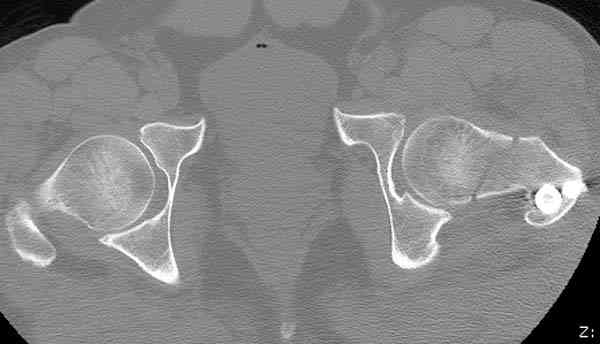

Здесь представлены снимки больного 65 лет, поступившего с диагнозом перелом

бедра после автоаварии.

В первый же день произведено антеградное штифтованием DePuy Trochanteric Nail.

На второй день (7) обнаружен пропущенный перелом,

сделаны Компьютерная Томограмма

и проведены шурурпы через и спереди штифта без удаления.